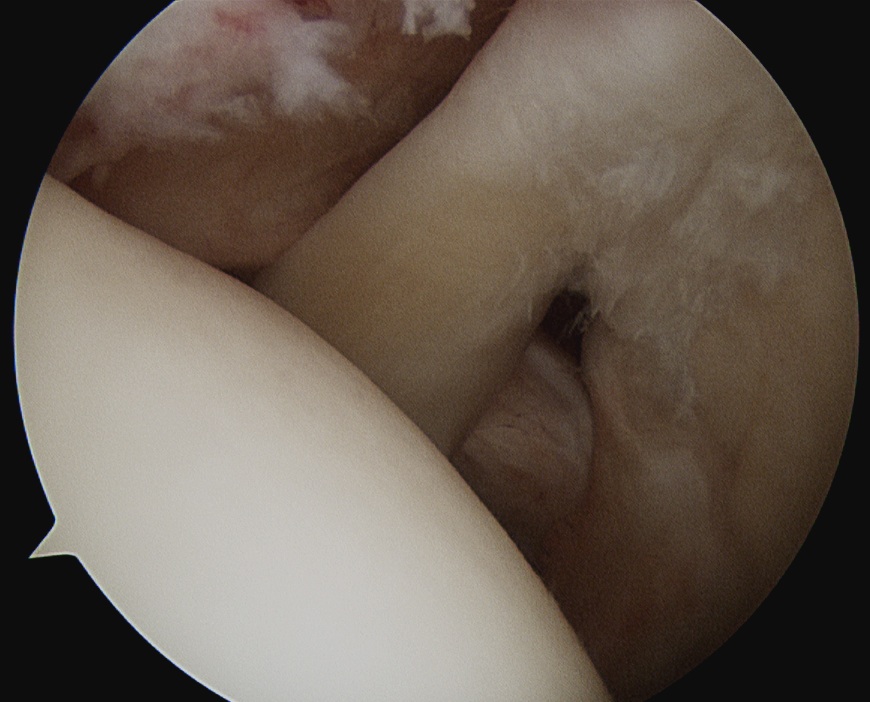

Arthroscopy

Hidden lesion

- assess subscapularis insertion thoroughly

- beware medial subluxation of the biceps

Medially dislocated biceps tendon with upper border subscapularis tear

Full thickness tear of subscapularis off insertion revealed with grasper